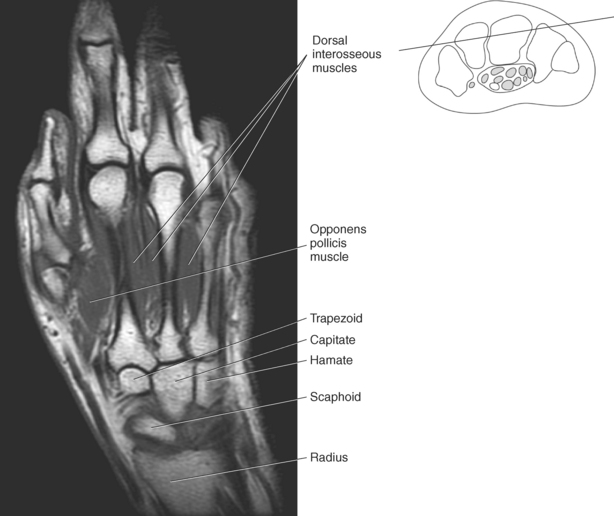

The bony anatomy of the wrist and hand consists of the distal radius and ulna, 8 carpal bones, 5 metacarpals, and 14 phalanges (Figure 9.101). Both the distal radius and ulna have a conical styloid process that acts as an attachment site for ligaments. The radial styloid process is located on the lateral surface of the radius, whereas the ulnar styloid process is located on the posteromedial side of the ulna. The carpal bones are arranged in proximal and distal rows. Located in the proximal row of carpal bones are the scaphoid (navicular), lunate (semilunar), triquetral (triquetrum), and pisiform bones. The pisiform is considered a sesamoid bone that is embedded in the tendon of the flexor carpi ulnaris. The distal row consists of the trapezium (greater multangular), trapezoid (lesser multangular), capitate (os magnum), and hamate (unciform) bones (Figures 9.102 through 9.114). The five metacarpals are small tubular bones with a proximal end (base), distal end (head), and shaft (body). The 14 phalanges that make up the fingers are short tubular bones. Like the metacarpals, each phalanx consists of a proximal (base), middle (body or diaphysis), and distal (head) portion. Each digit consists of 3 phalanges (proximal, middle, and distal), except for the thumb (first digit), which has only 2 phalanges (proximal and distal). The articulation of the phalanges of the second through fifth digits creates three interphalangeal joints: the metacarpophalangeal (MCP) joints classified as condyloid joints, proximal interphalangeal (PIP), and distal interphalangeal (DIP). The proximal and distal interphalangeal joints are classified as hinge joints (Figure 9.101). The first digit, which consists of 2 phalanges, has just two joints: the MCP joint, classified as a saddle joint, and an interphalangeal joint, classified as a hinge joint (Figure 9.101).

The metacarpal muscle group includes the interossei and lumbrical muscles. There are seven short interossei muscles in the metacarpal muscle group: three single-headed muscles located on the palmar surface and four double-headed muscles located on the dorsal surface (Figure 9.141, A and B). The four palmar interossei muscles arise from the first, second, fourth, and fifth metacarpals and insert on the corresponding proximal phalanges, frequently radiating into the corresponding tendons of the dorsal aponeurosis. These muscles are responsible for flexion at the MCP joints and extension at the interphalangeal joints. The dorsal interossei arise by two heads from the sides of the five metacarpal bones to insert on the proximal phalanges and radiate onto the dorsal aponeurosis. Like their palmar counterparts, the dorsal interossei flex at the MCP joints and extend at the interphalangeal joints. The four small lumbrical muscles arise from the tendons of the flexor digitorum profundus and pass to the radial side of the corresponding finger to insert on the extensor expansion covering the dorsal surface of the finger (Figure 9.142). The lumbricals flex the first phalanges at the MCP joints and extend the second and third phalanges at the interphalangeal joints.